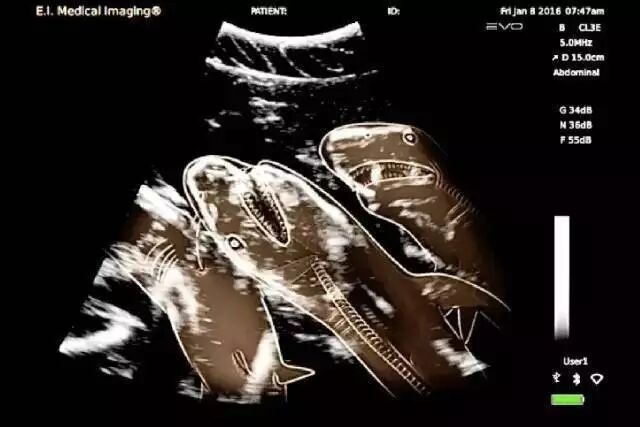

怀孕的虎鲨

奇趣百科 涨姿势 · 17种怀孕动物X光照片,大开眼界!-怀孕期